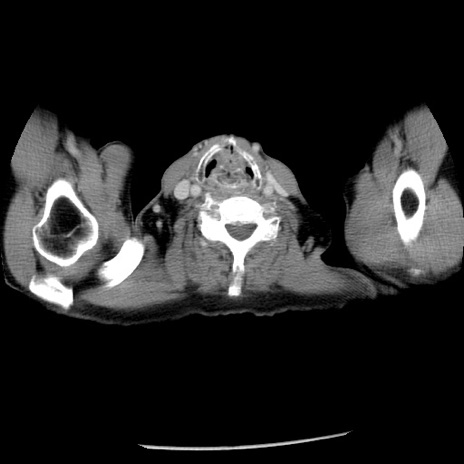

冠状断像

【症例】80歳代男性

【主訴】嘔吐

【現病歴】昨晩2回嘔吐あり、今朝になっても嘔吐あり。来院。

【既往歴】胃潰瘍

【身体所見】意識清明、BT 37.6℃、BP 166/95mmHg、HR 100bpm、SpO2 97%、腹部:平坦・軟、腸蠕動音聴取良好、圧痛なし。

【データ】WBC 21900、CRP 1.46